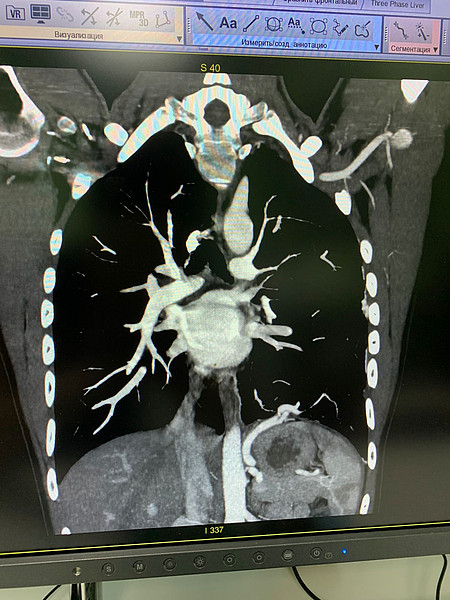

IMG-20211226-WA0003.